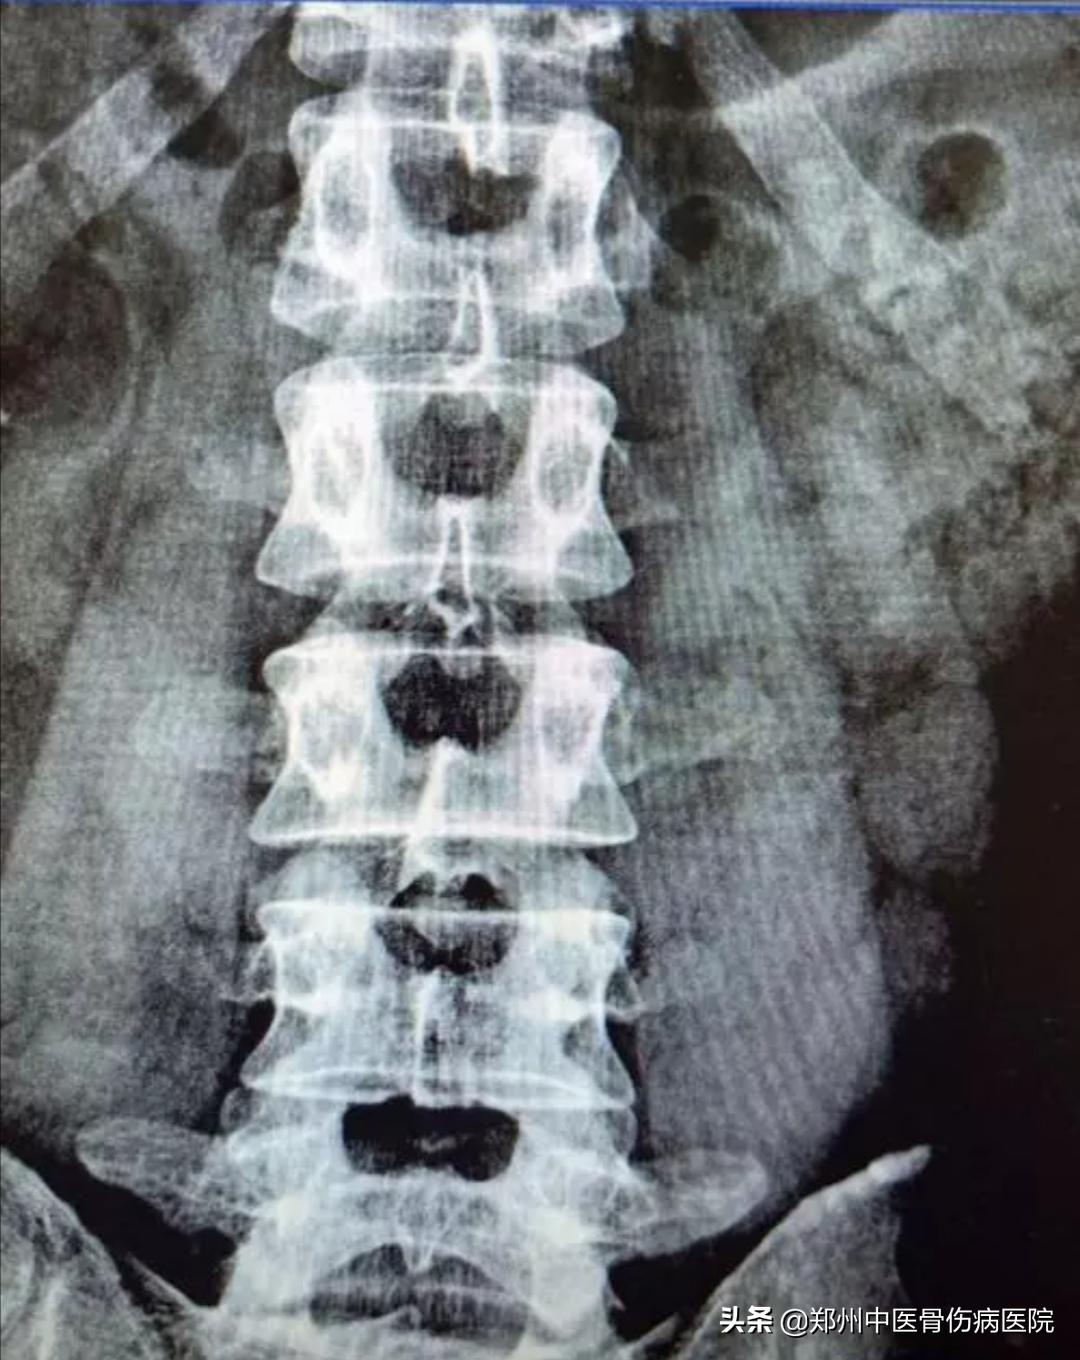

腰椎小关节错位 ,常见于急性腰扭伤。腰椎小关节错位,就是指腰椎的小关节不稳,多由于外伤、退行性改变及先天发育等因素所造成,并引起腰部疼痛、活动受限,以及其他一系列症状者。

建议到医院进行检查,先拍一个腰椎部位的片子,根据实际错位情况再进行关节复位的治疗。并在医生的指导下,配合进行相关的康复训练,有助于恢复。